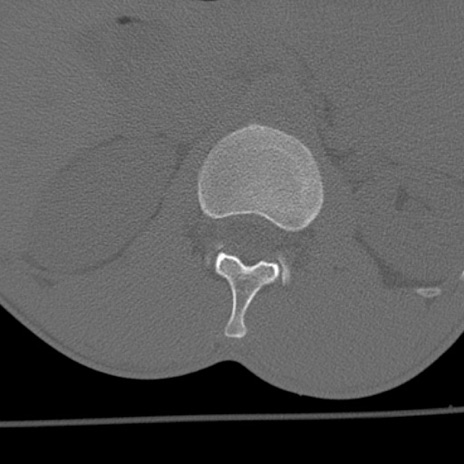

症例3 腰椎CT(横断像)

腰椎CT